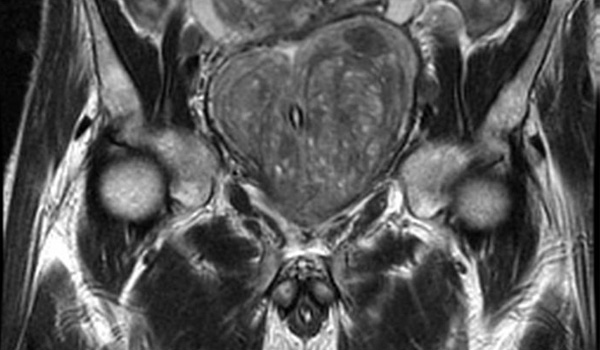

Imágenes por resonancia magnética en la detección del cáncer de próstata:  revisión sistemática y metanálisis

Los resultados de esta revisión sistemática y metanálisis sugieren que la integración de la resonancia magnética en las vías de detección del cáncer de próstata se asocia con un número reducido de biopsias innecesarias y un sobrediagnóstico de cáncer de próstata insignificante, al tiempo que se mantiene la detección de cáncer de próstata clínicamente significativo en comparación con la detección solo con PSA. JAMA Oncol,  5 de abril de 2024